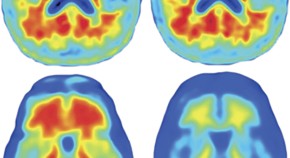

Studies of preclinical Alzheimer disease (AD) have unexpectedly shown amyloid-β deposition and/or AD-like neurodegenerative changes in the brains of a high proportion of clinically normal elderly individuals. As two recent reports illustrate, imaging and fluid biomarker studies in these individuals are yielding new insights into the pathophysiology of cognitive ageing.